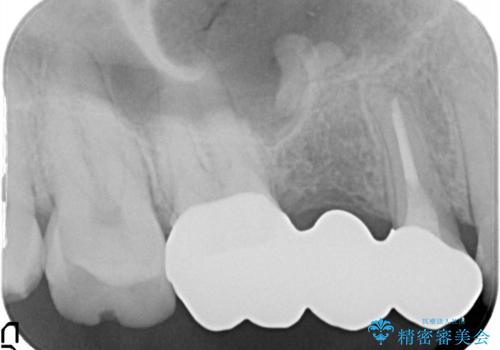

根の治療を行いその後にオールセラミックブリッジを装着する計画となりました。

以前は保険治療で作られた金属のブリッジを装着されていましたが、オールセラミックブリッジを装着することにより、審美的にも改善されました。